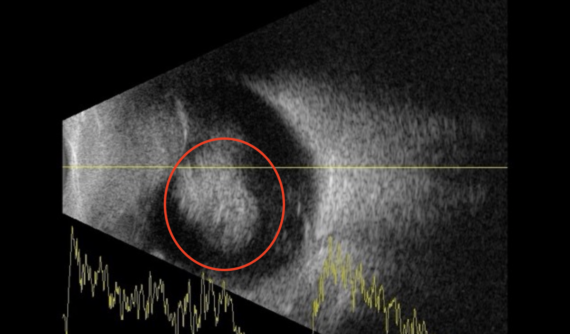

Para profundizar en la situación del ojo derecho de Thor, optamos por realizar una ecografía, una herramienta que nos permite examinar detalladamente diversas estructuras oculares, proporcionando información más precisa y facilitándonos la tarea de llegar a un diagnóstico específico sobre la enfermedad ocular que afecta al paciente.

Los resultados de la ecografía en el ojo izquierdo de Thor fueron excepcionales, revelando una condición completamente normal, sin ninguna alteración detectada. En cambio, en el ojo derecho, se observó una masa circular (destacada en la foto con un círculo rojo), indicativa de la probable presencia de un tumor intraocular que se extendía en la cavidad vitrea.